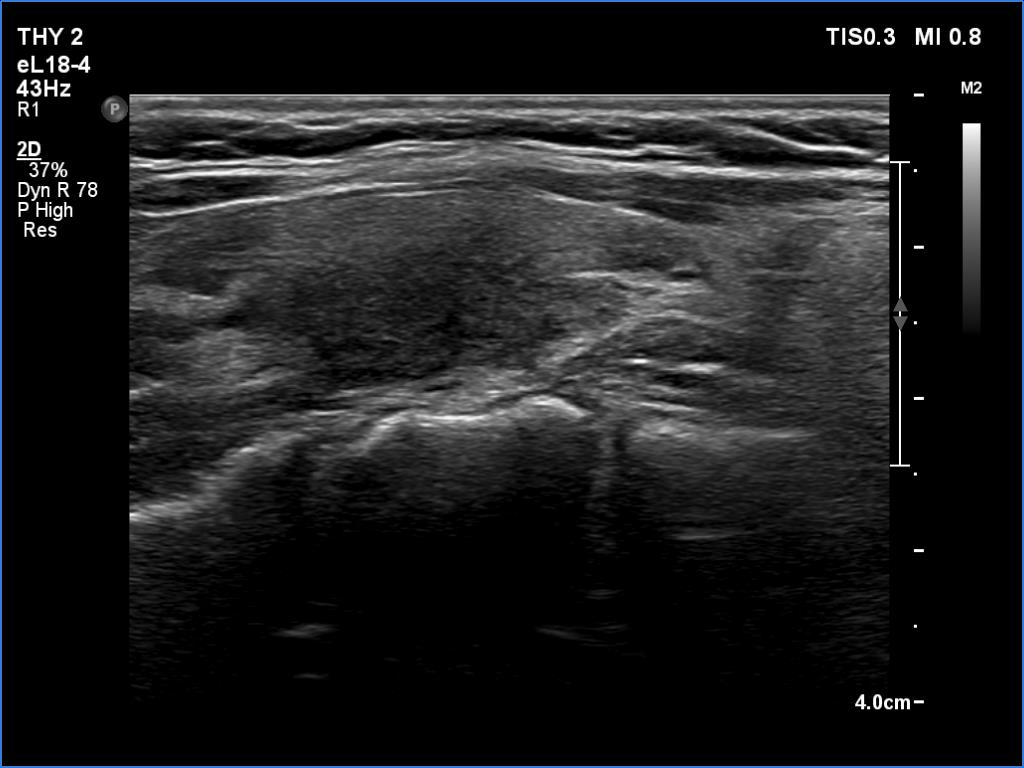

Second examination 6 years later (second row of images):

Clinical data: The TSH was regularly checked and remained within the normal range in the past 6 years on daily 50 microgram levothyroxine. Ultrasound was performed in every two years and the pattern was the same as at the first examination so far.

Palpation: no abnormality.

Laboratory tests: TSH 2.38 mIU/L on daily 50 microgram levothyroxine.

Ultrasonography. The right lobe was echonormal and had several minimally-moderately hypoechoic islets which presented relatively sharp borders. A moderately hypoechoic lesion has appeared in the left lobe. The lesion had blurred borders and was avascular.

Additional tests: aTPO 7 U/mL, CRP 0.8 mg/L.

Aspiration cytology resulted in Hashimoto's thyroiditis.

Suggestion: daily 50 microgram levothyroxine. Repeat ultrasound in 3 to 6 months.